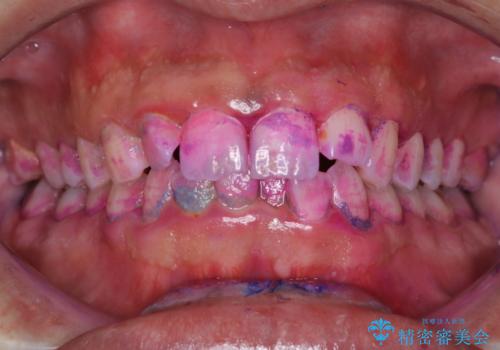

結婚式前にクリーニング希望の方